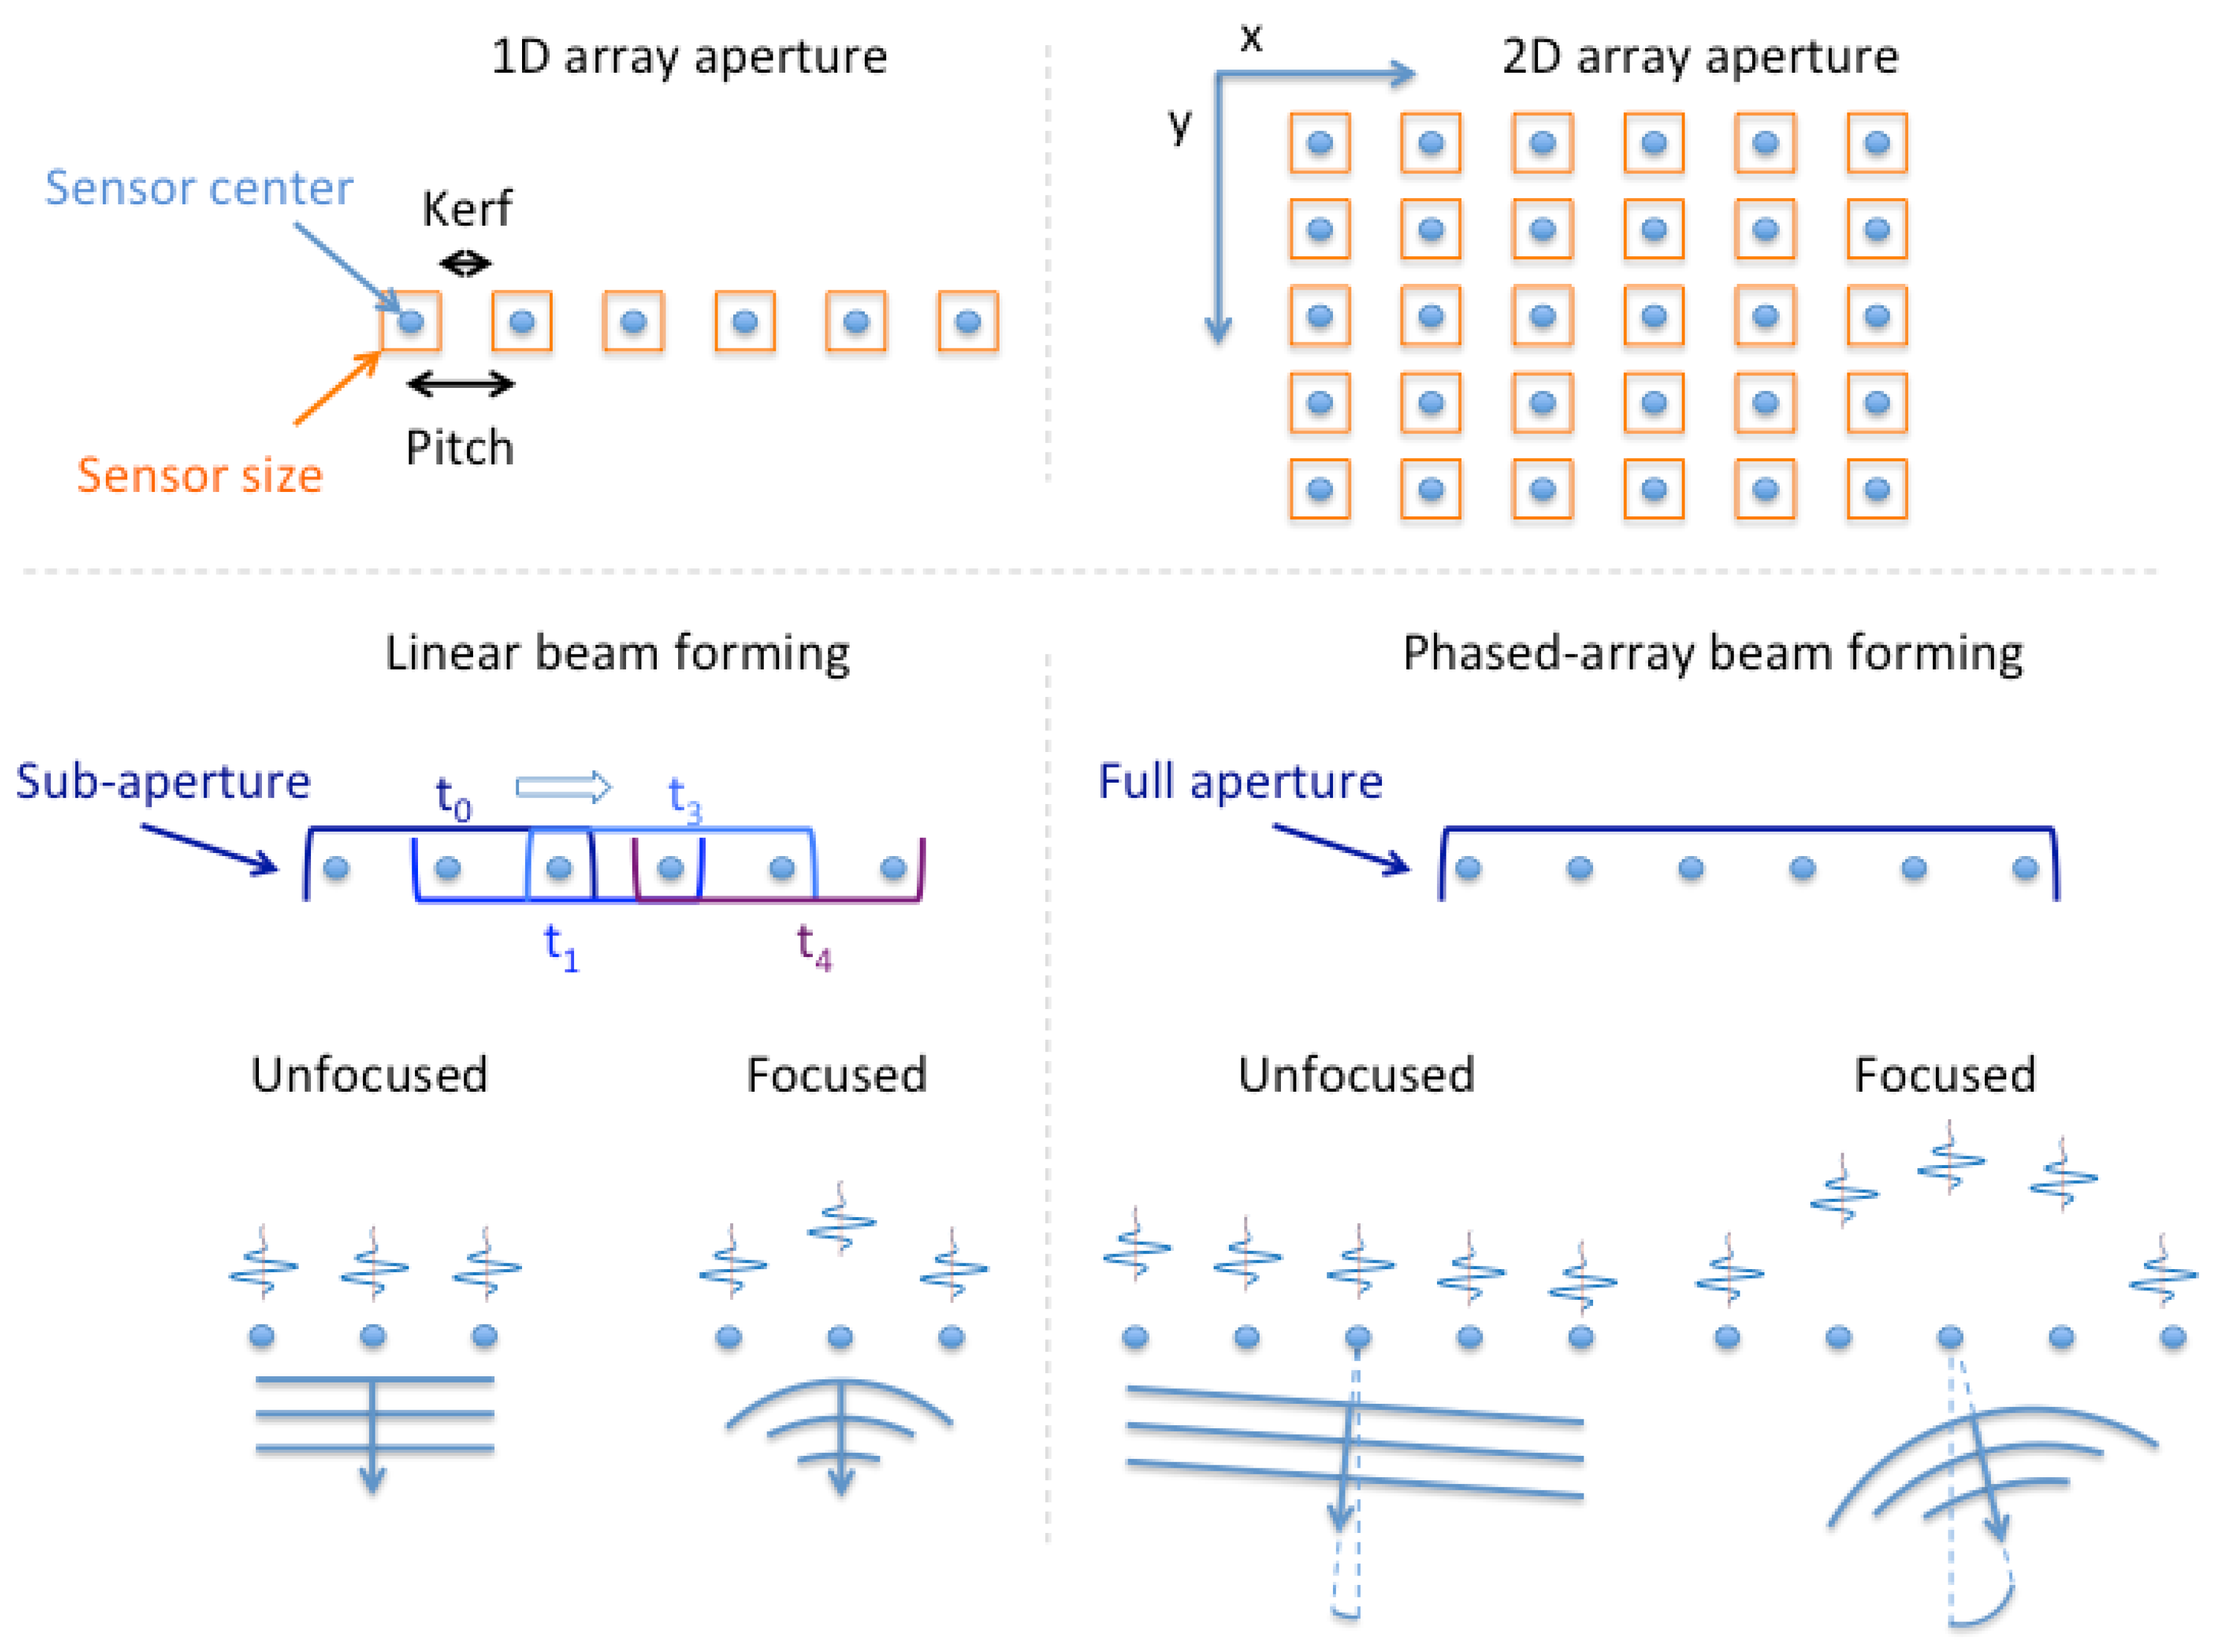

Wireless Bluetooth Speaker for Panasonic Eluga Z Ultra Boost Bass DJ Sound Portable Home Speaker Audio Line in TV Supported USB FM AUX Cable sale, Wireless Bluetooth Speaker for Acer Liquid Jade Z Ultra Boost Bass DJ Sound Portable Home Speaker Audio Line in TV Supported USB FM AUX Cable sale, Z TONE Buffer Boost sale, Z TONE Buffer Boost sale, Wireless Bluetooth Speaker TG113 For HTC Desire Z Ultra Boost Bass sale, Shopnet Sony Xperia Z Ultra Bluetooth Ultra Boost Bass with DJ sale, Sound Blaster Z PCIe Gaming Sound Card with High Performance Headphone Amp and Beam Forming Microphone sale, Shopnet Sony Xperia Z Ultra Bluetooth Ultra Boost Bass with DJ sale, Z TONE Buffer Boost sale, Wireless Bluetooth Speaker for Samsung Z Ultra Boost Bass DJ Sound sale, Z Dialogue Clarifying Sound Bar with Patented Hearing Technology sale, Sound Blaster Zx PCIe High Performance Sound Card sale, Mindray Vetus E7 Ultrasound Machine Best Price UDS sale, A wearable cardiac ultrasound imager Nature sale, Buy Wanzhow super powerful ultra sound boost wireless speaker with sale, Galaxy S23 s How to Boost The Audio For Louder Sound sale, M9 General Imaging Ultrasound Systems Mindray Global sale, Shopnet Sony Xperia Z Ultra Bluetooth Ultra Boost Bass with DJ sale, Sound Blaster Z Review Solid Audio Quality and Good Value for Gamers sale, Functional ultrasound imaging Wikipedia sale, Goldwell Stylesign Ultra Volume 4 Double Boost Intense Root Lift Hairspray 6.2 Oz. Pack Of 2 sale, Samsung Galaxy S23 Ultra Audio test DXOMARK sale, Bose QuietComfort Ultra Earbuds Review Slightly Better Than Last sale, Samsung Galaxy Z Fold5 Volume Controls Verizon sale, Buy LIFE MUSIC unique speaker best sound with deep bass portable sale, M9 General Imaging Ultrasound Systems Mindray Global sale, Samsung Galaxy S23 Ultra How To Make Device Louder sale, Bose QuietComfort Ultra Earbuds Review PCMag sale, Mindray Vetus E7 Veterinary Ultrasound Scanner IMV Imaging sale, Applied Sciences Free Full Text Practical Guide to Ultrasound sale, 33 Moto Z Play Stock Photos High Res Pictures and Images Getty sale, Ultra Volume booster Loud Apps on Google Play sale, Getting it bright How ultrasound enhancing agents GE HealthCare sale, Use Dolby Atmos and other audio features on your Galaxy phone sale, Early Identification of Takotsubo syndrome in the emergency sale, Galaxy Z Flip 5 Review Its Big Cover Screen Disappoints sale, Goldwell Ultra Volume Double Boost 4 for hair in 2023 Goldwell sale, Buy FIXTSON 887 Power Boost High Sound Blast With Ultra 3D Bass sale, Ectopic expression of a mechanosensitive channel confers sale, Diagnostic Medical Sonography Tarrant County College sale, Bose QuietComfort Ultra Earbuds Review Slightly Better Than Last sale, Samsung Galaxy Z Fold 5 vs Galaxy S23 Ultra which premium to go sale, Samsung Galaxy Boost Disney Offer Samsung UK sale, Samsung Galaxy S22 Ultra review All the phone you need Digital sale, Spectrum Mobile to Offer Samsung s New Galaxy Z Fold5 Galaxy Z sale, Welcome to Scanbooster the world s first realistic Ultrasound sale, Protective Case for Moto Insta Share Projector Motorola Hasselblad True Zoom Camera JBL SoundBoost SoundBoost2 Moto Mod Moto Z Ultra Slim Compact sale, Logitech Z 5500 Speakers for Gaming and Digital Multimedia Review sale, Samsung Galaxy S22 Ultra review All the phone you need Digital sale, How to Boost Your Volume Sound on Windows PC sale.